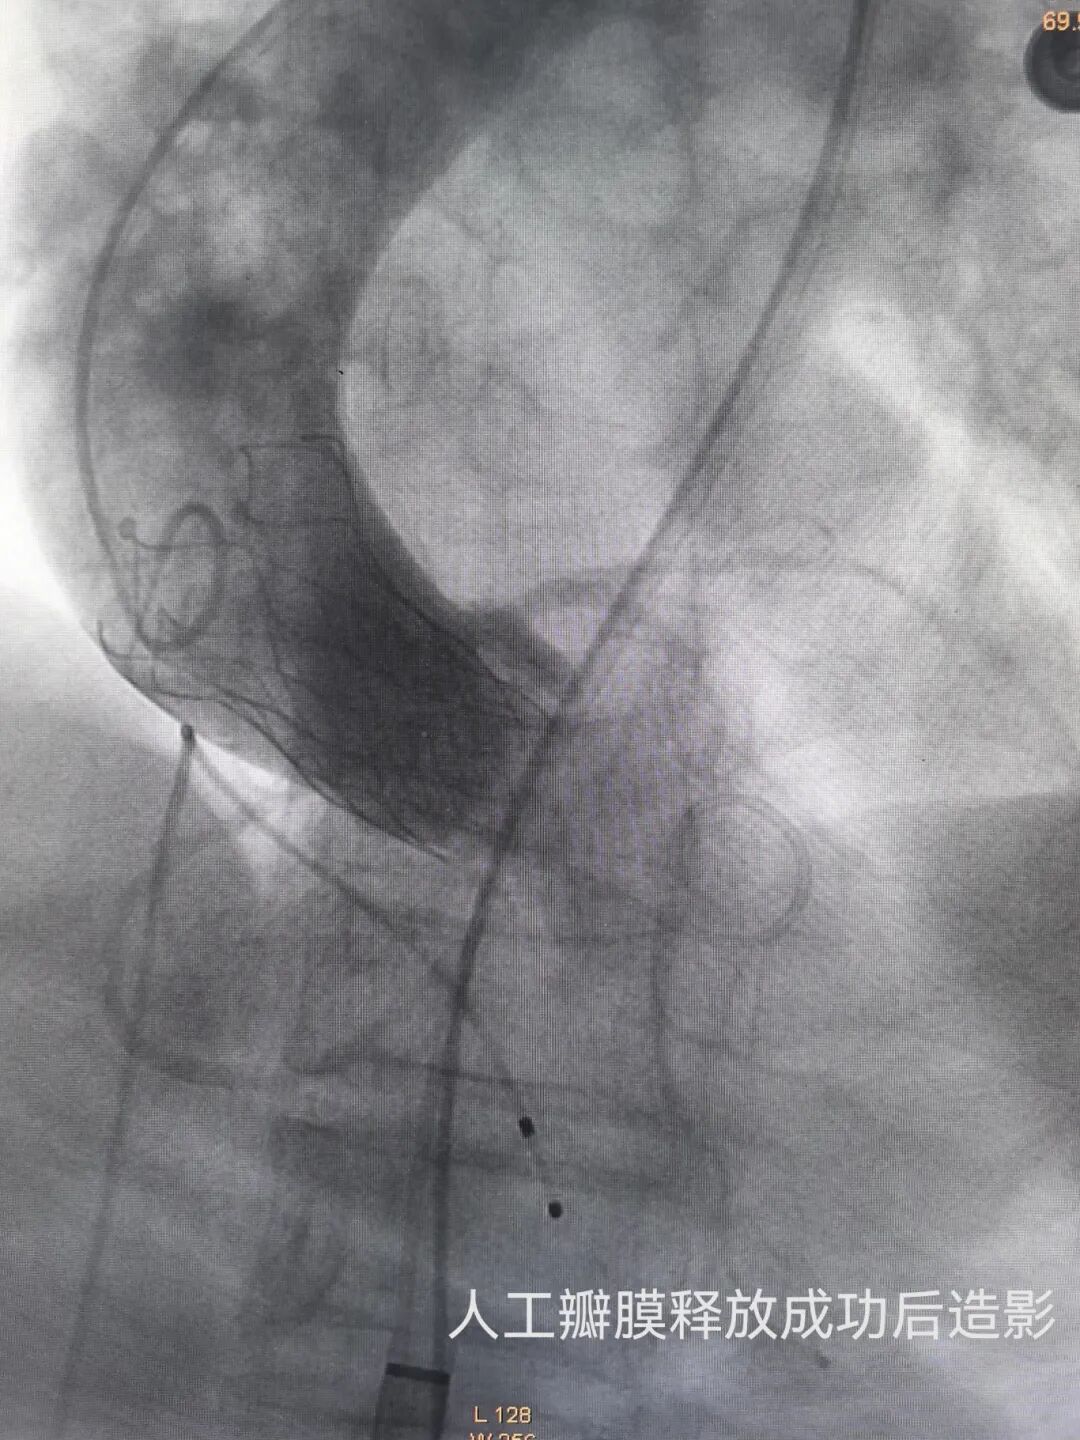

手术当日,在中山大学第一附属医院广西医院袁军教授的指导下,河池市第三人民医院心血管内科手术团队通过股动脉穿刺建立微创通路,将人工瓣膜精准送达患者病变主动脉瓣位置,在临时起搏器保护及实时造影监测下完成瓣膜释放。整个手术历时仅1小时余,术中患者生命体征平稳,几乎无明显出血。术后复查显示,人工瓣膜启闭功能良好,平均跨瓣压差降至15mmHg,术后症状明显好转。

术前术后